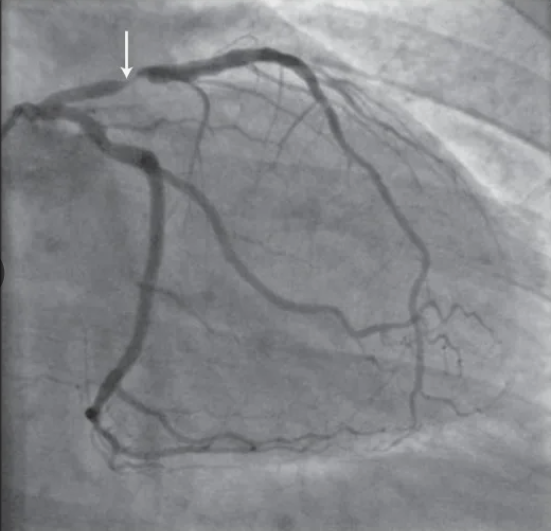

Женщина 45 лет, первая операция - коронарное стентирование, выполнена 9 лет назад - установлен стент в переднюю нисходящую артерию. То есть в возрасте, который для женщин совершенно нетипичен в отношении развития атеросклероза.

Уровень холестерина ЛПНП был не оптимальный, но и не какой-то запредельный, чтобы списать именно на него столь ранний клинически значимый атеросклероз. Диабета нет, не курила, артериальную гипертонию не вполне оптимально, но лечила. После стентирования начала принимать статин в приличной дозе, холестерин ЛПНП был не такой, как надо, но все же уменьшился почти в 2 раза: стал около 2,5 ммоль/л.